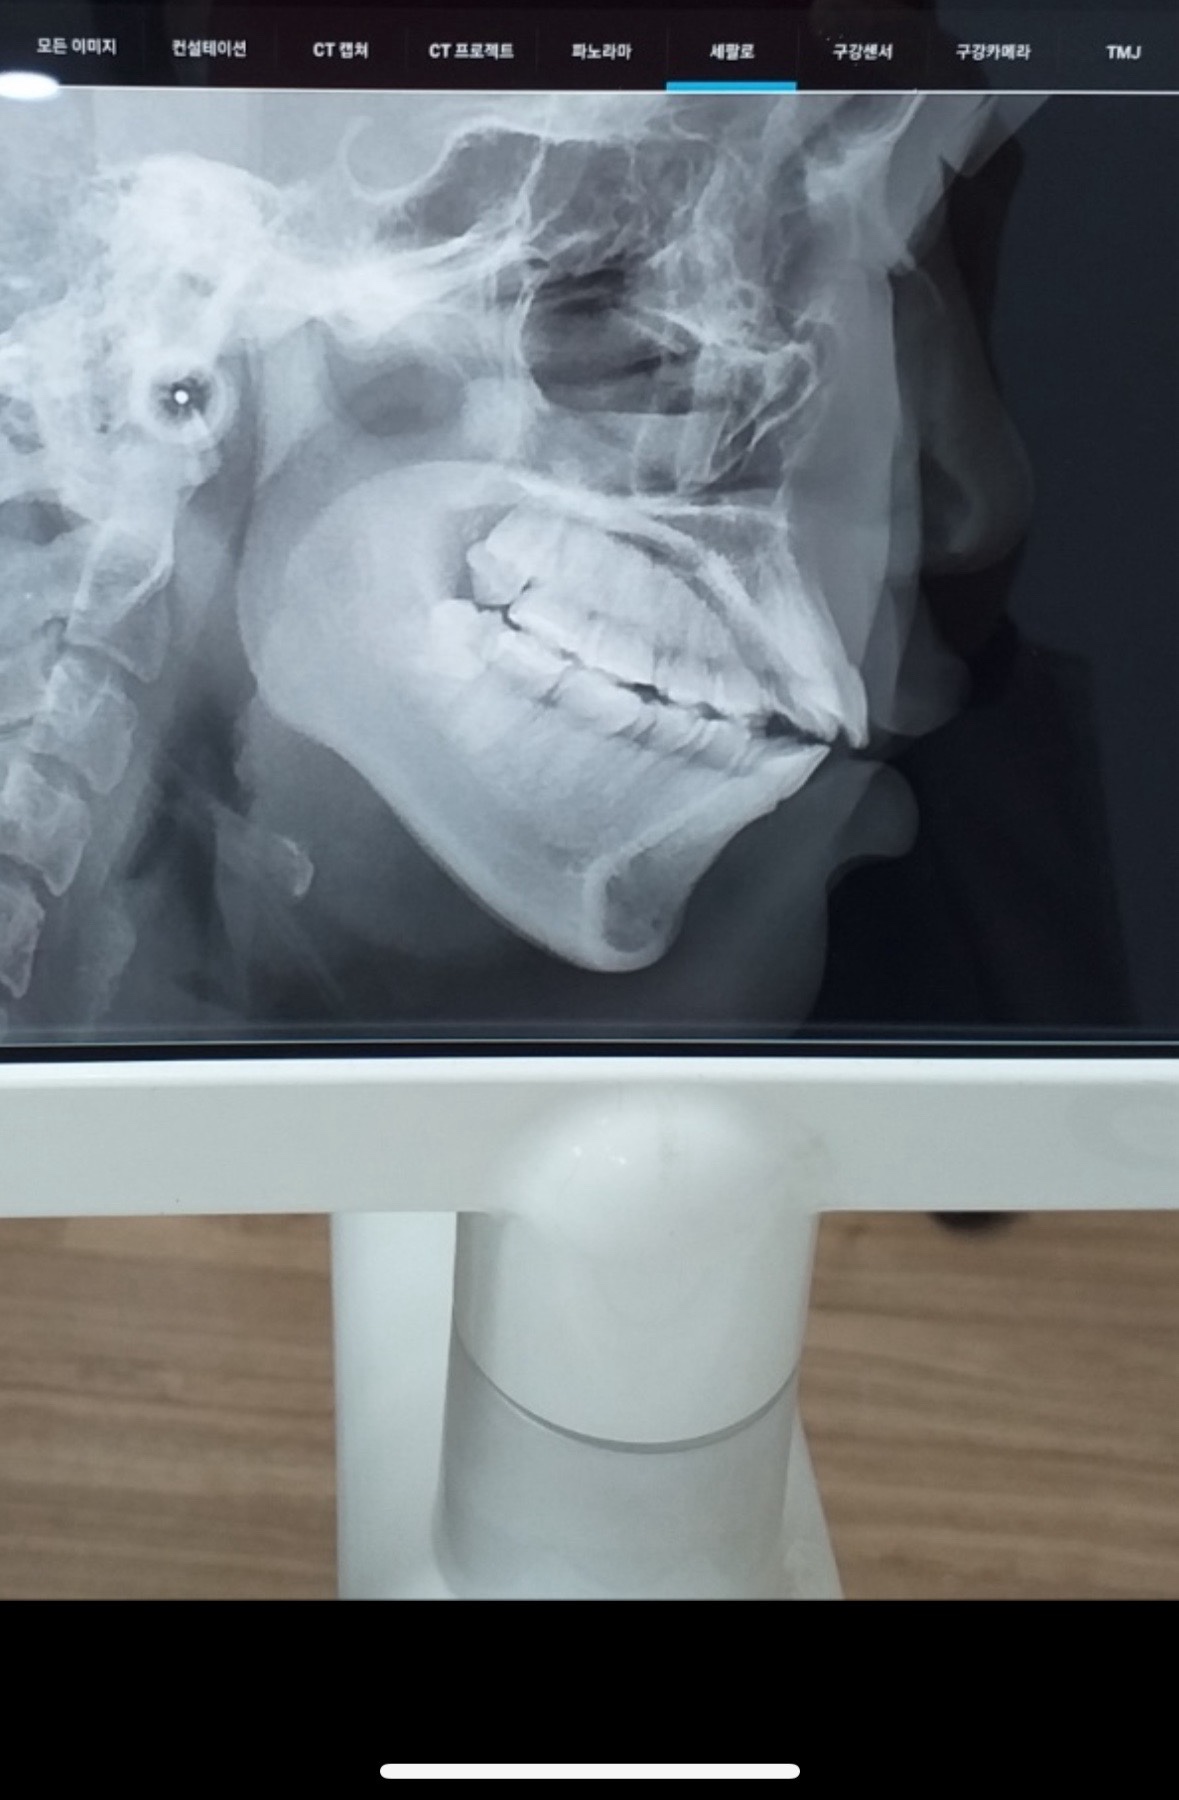

교정전에 찍은거긴한데 갑자기 궁금하넵 긴편이야 짧은퍈이야?

짧은편 같은데 턱뼈 작다 이런 말 안 해줘써?